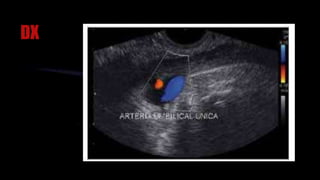

ARTERIA UMBILICAL ÚNICA

La anomalía más frecuente del CU es la

presencia de sólo dos vasos, una arteria y

una vena, denominada arteria umbilical única

•Se cree que es causada por atrofia de una

arteria previamente normal o el fallo del

desarrollo de una de las arterias umbilicales.

• La arteria más frecuentemente ausente es la izquierda. En

casi el 20% de los casos de arteria umbilical única se hace el

diagnóstico prenatal en una población de alto riesgo en que se

suele asociar con anormalidades cromosómicas. La trisomía

18(sx Eduar) es la anomalía cromosómica más asociada con

una arteria umbilical única

DX